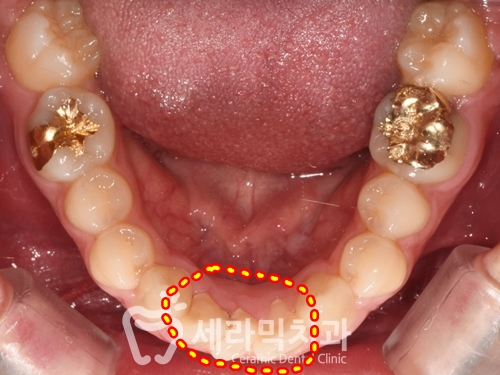

① 과개교합, 치아배열 좋지 않음

④ 상하 어금니 교차교합

위쪽 어금니는 안쪽으로,

아래쪽 어금니는 바깥쪽으로, 서로 반대로 기울어져 있습니다.

⑤ 아래 앞니가 1개 없음

통상 '앞니' 라 부르는 '전치'는 4개로 구성되어 있는데,

사례자분은 아래 앞니가 선천적으로 1개가 부족합니다.

● 과개교합, 돌출입, 어금니 교차교합 치아교정전후 치열 변화 ●

과개교합과 돌출입, 치열불규칙 치아교정전후 변화 결과를

정면, 측면, 반측면 외에도 다양한 각도로 확인하실 수 있습니다.